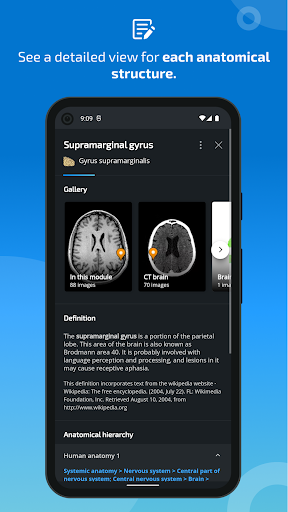

* تحسين رؤية تعريفات الأجزاء التشريحية

- يتم الآن عرض المصطلحات المتعلقة بالهيكل التشريحي في عرض التفاصيل - تمت إضافة

* تقديم الجداول في تعريفات الهياكل التشريحية لتحسين هيكلة البيانات

* تحسين عرض التفاصيل للأجزاء التشريحية لتسهيل التعرف عليها في صور الوحدات الحالية والوحدات الأخرى.